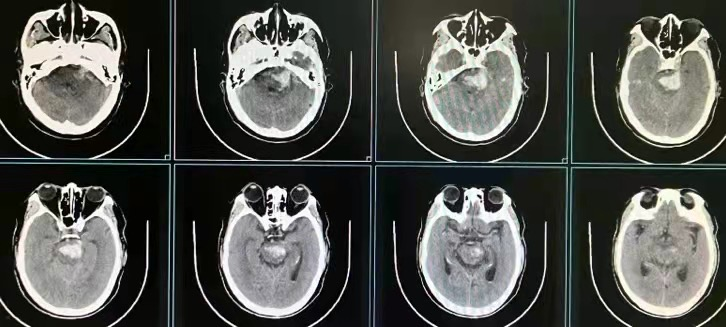

脑干血肿清除术前CT

脑干血肿清除术后CT

开展经鼻蝶手术治疗垂体瘤、颅咽管瘤、鞍结节脑膜瘤等;3D辅助内镜脑内血肿清除术;脑干血肿内镜清除术等。